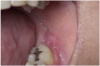

Secondary malignancies related to therapeutic immunosuppression in susceptible individuals include de novo squamous cell carcinoma of the skin and lip (Figure 25).16 Secondary malignancies related to immunosuppression-induced reactivation of oncogenic viruses include Kaposi sarcoma (Figure 26), lymphoproliferative diseases (Figure 27), Hodgkin's and non-Hodgkin's lymphomas, and spindle-cell sarcoma (Figure 28).16

Figure 26. Human Herpesvirus-8-related Kaposi Sarcoma of the Palate in a Patient 4 Years After Renal Transplantation.

Figure 26